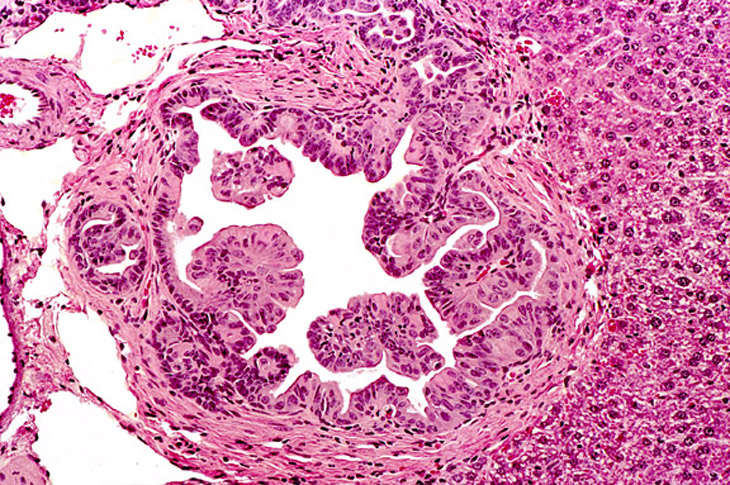

Cholangiocarcinoma in a 4-week old AL-ras x AL-myc mouse.